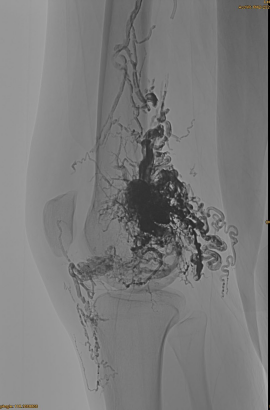

ข้อมูลพื้นฐานของผู้ป่วย: หญิง, 36 ปี; avm pelvis, สะโพก, หัวเข่า, osg ซ้าย, pre pre - embolizations

ผลิตภัณฑ์ที่ใช้: 3PCS LAVA-34,14PCS LAVA-18

DSA เริ่มต้น:

ผลลัพธ์สุดท้าย:

แทบจะไม่มีการไหลออกของหลอดเลือดดำ: